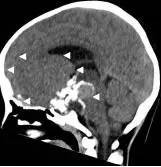

病例1:患儿男性,9岁。因反复出现意识丧失、视力下降半年收入院。入院后CT及 MRI显示颅内有形态不规则、“超大型”的颅咽管瘤,最大径约10厘米,见图1、图2。

图1.术前CT显示典型的囊性颅咽管瘤